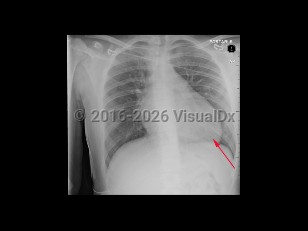

Acute coronary syndrome

Aortic dissectionAortic dissection

Congestive heart failureCongestive heart failure

Hypertrophic cardiomyopathyHypertrophic cardiomyopathy